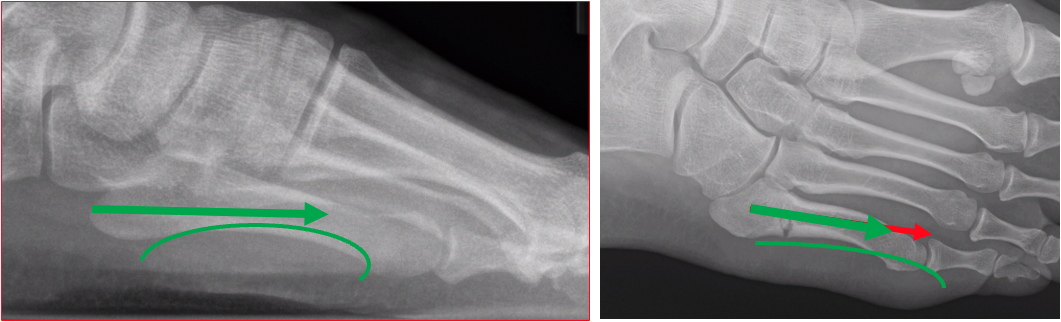

Keep the screw length as long as you can, unless you have a plantar curve on the lateral view. In my observation, too long a screw will distract the fracture with cases that have a plantar curve. Average screw length range from 50-55mm, in my experience. See Figure 5.